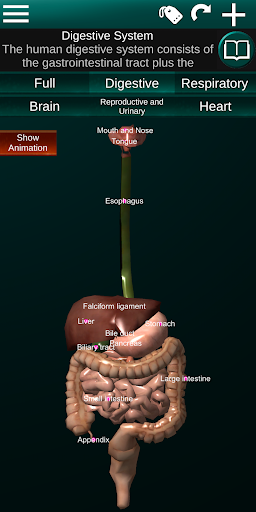

* Sistem pencernaan, termasuk lambung, usus kecil, usus besar, dan animasi sistem ini.